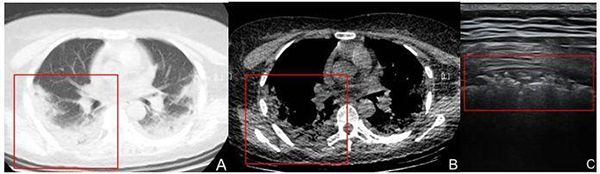

2.3.4.2 COVID-19进展期:一般患者发病后5~8天,伴有咳嗽,气短,发热等临床症状[6]。超声于肺周可见胸膜线中断;胸膜线下可见多发、连续斑片样、结节样、长条样低回声实变影,形态不规则;实变肺组织内可见细支气管充气征,病灶下可见多条B线或融合B线(呈瀑布征)[7],位置固定。单个或多个肺区累及,以双肺后下肺野为著。部分病灶相邻胸膜腔内可见局限性胸腔积液及增厚胸膜(图11)[8]。CDFI显示实变区域血流信号较常规肺炎病灶稀少。

注:A和B:分别是肺窗、纵膈窗CT图像,COVID-19患者,女,42岁,发热7天,体温最高38.5℃,HRCT显示右肺后上野区肺周处胸膜下条带样实变影,内密度不均匀(红方框所示)。C:超声线阵探头显示右后上肺野胸膜线中断、消失,胸膜下可见条带样暗淡实变肺组织,其内可见散在细支气管充气征,后伴B线(红方框所示)

图11 COVID-19进展期影像表现